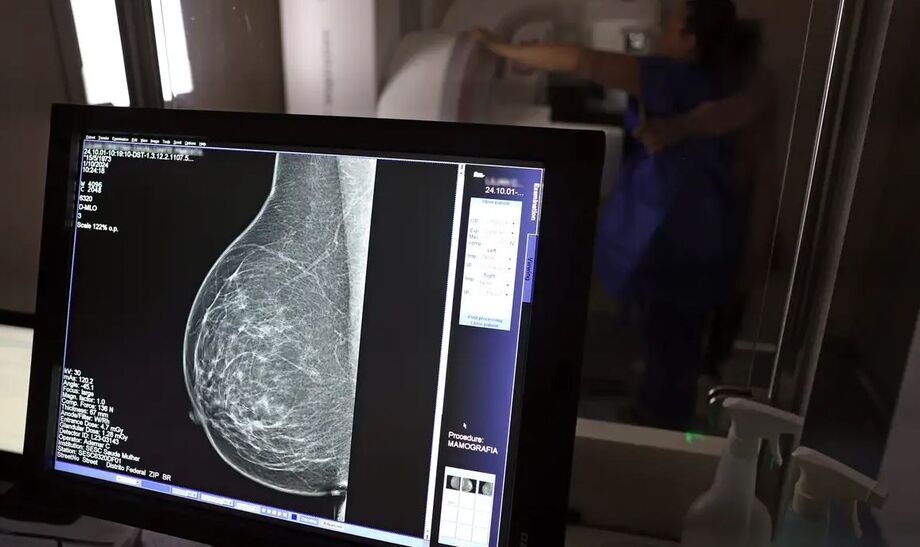

Segundo o Instituto Nacional de Câncer (Inca), mais de 73 mil mulheres são diagnosticadas com câncer de mama por ano no Brasil. O diagnóstico precoce é considerado uma das ferramentas mais eficazes para reduzir a mortalidade.

“O que é efetivo na redução da mortalidade é você descobrir o tumor antes de ter sintoma clínico. Quanto menor o tumor, melhor para a gente descobrir o tratamento e maior a chance de cura. E a gente só consegue fazer isso com exames de imagem”, destaca Ivie.

Um dos dados mais impactantes trazidos por Ivie Braga de Paula é sobre a taxa de cura nos casos em que o câncer de mama é diagnosticado ainda em estágio inicial.

“Se o tumor tem menos de 1 cm, a chance de cura é de 95% em cinco anos, mesmo se for do tipo mais agressivo. E esses tumores só vão ser detectados na mamografia. Essas pessoas que têm que ir fazer mamografia são mulheres saudáveis. Não são mulheres doentes”, afirma.